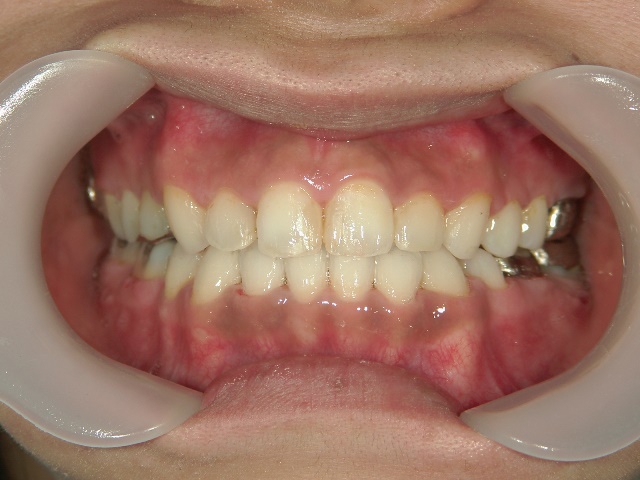

矯正歯科 治療後矯正歯科 全顎ワイヤー矯正 治療後矯正歯科(全顎ワイヤー矯正)治療後

全顎ワイヤー矯正 症例(18)

30歳女性 浜松市北区在住

治療期間3年4ヶ月

主訴:前歯の歯並びが気になる。

矯正歯科 治療後